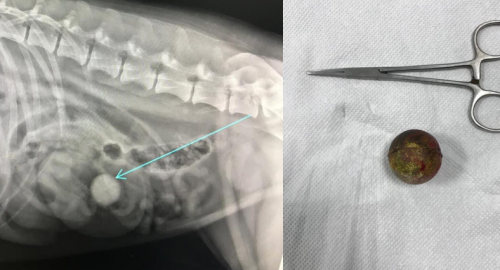

RADIOLOGIA